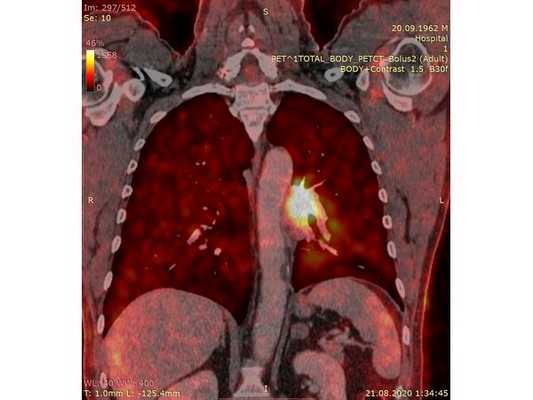

31.07.2020 мужчина 57 лет обратился в Клиническую больницу № 2 АО ГК МЕДСИ с данными компьютерной томографии, где выявлено центральное новообразование в корне нижней доли левого лёгкого.

Чтобы провести первичное стадирование опухоли, пациенту проведена позитронно-эмиссионная томография в сочетании с компьютерной томографией (ПЭТ-КТ). По данным исследования, выявлена метаболически активная опухоль в корне левого лёгкого с бугристыми контурами размерами 41 х 43 мм. В толще опухоли проходят нижнедолевой бронх и бронх 6-го сегмента левого лёгкого, просветы бронхов значительно сужены. Нижняя доля левого лёгкого уменьшена в размерах за счёт того, что сегменты 6, 9 и 10 субтотально (частично) инфильтрированы и безвоздушны. Лимфатические узлы корня лёгкого и средостения не увеличены в размерах и не накапливают радиофармпрепарат (РФП), который был введён пациенту перед обследованием внутривенно. Других очаговых образований и очагов гиперметаболизма в организме не обнаружено.

При этом отмечено, что опухоль распространяется в средостение по нижней стенке левого главного бронха и широко прилежит к нижнегрудному отделу аорты (по заключению специалиста ПЭТ-КТ — имеется инвазия опухоли в ткани средостения и возможное врастание в стенку аорты). При самостоятельном пересмотре изображений отмечено, что "опухолевая" ткань, которая распространяется по нижней стенке левого главного бронха в средостение, не накапливает РФП (т. е. не является злокачественной), а стенка аорты в области "инвазии" опухоли имеет ровный чёткий контур и адвентициальную границу, что также свидетельствует об отсутствии онкологического процесса в этой области.